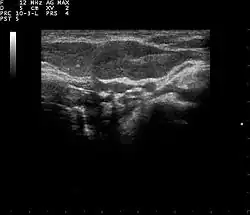

Muscoesqueleto

Tendones, músculos, nervios, ligamentos, masas de tejidos blandos y superficies óseas. Es una alternativa a la radiografía en la detección de fracturas de muñeca, codo y hombro para pacientes de hasta 12 años.

Endocrinología, laringología

La mayoría de las estructuras del cuello, incluyendo las glándulas tiroides y paratiroides, los ganglios linfáticos y las glándulas salivales, se visualizan bien mediante ultrasonidos de alta frecuencia con imágenes de alta calidad. La ecografía es una modalidad de imagen con especial incidencia en lesiones de tiroideas.[19]